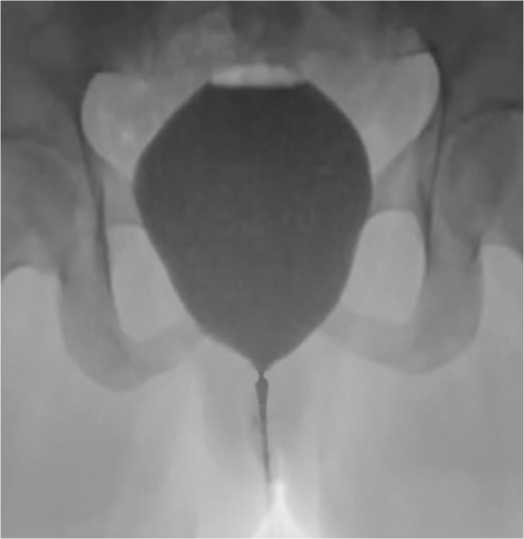

При выполнении микционной цистографии выявлено сужение просвета дистальной уретры протяженностью до 1,5 см (рис. 2).

Рис. 2. Микционная цистоуретрография до оперативного лечения

Fig. 2. Voiding cystourethrography before surgical treatment

Микционная цистоуретрография – без особенностей, признаков стриктуры уретры не определяется (рис. 7).

Рис. 7. Микционная цистоуретрография после оперативного лечения

Fig. 7. Voiding cystourethrography after surgical treatment